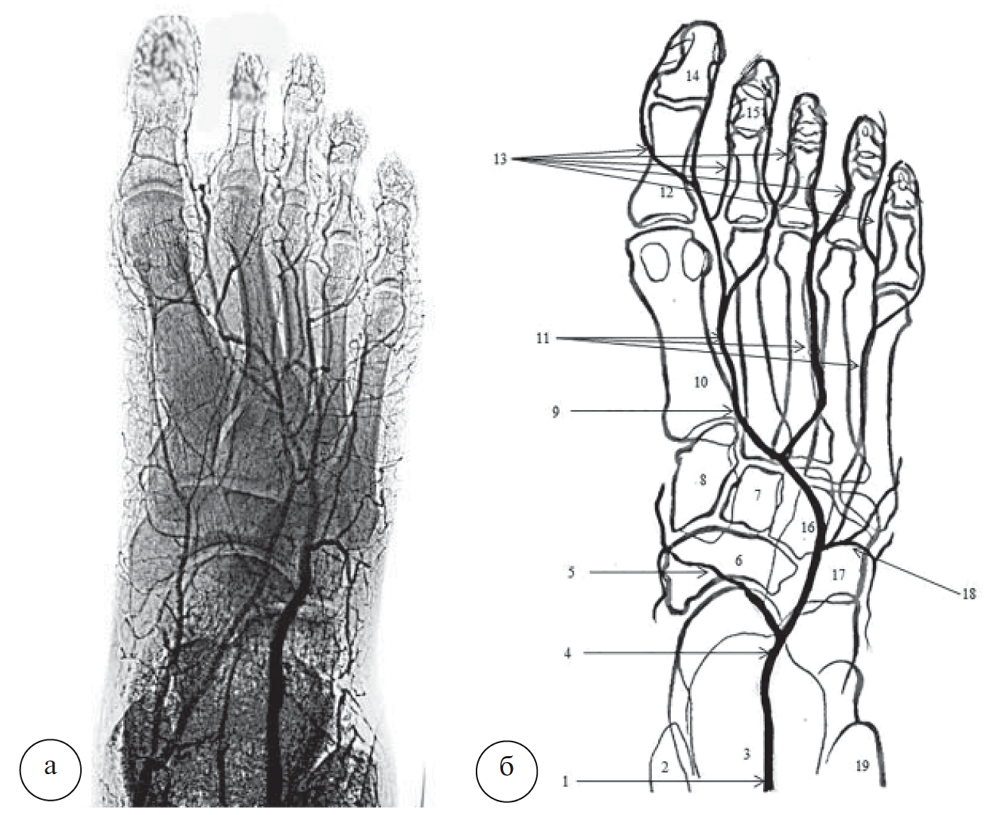

Вариант медиальной архитектоники ТАС с выраженным изгибом ствола в медиальную сторону представлен на рисунке 3.

Рис. 3. Вариант архитектоники тыльной артерии стопы с изгибом ствола в медиальную сторону: a – ангиорентгенограмма; б – схема ТАС и ее ветвей (подошвенные артерии на схеме отсутствуют). 1 – передняя большеберцовая артерия; 2 – медиальная лодыжка; 3 – таранная и пяточная кости; 4 – тыльная артерия стопы; 5 – ладьевидная кость; 6 – медиальные предплюсневые артерии; 7 – промежуточная клиновидная кость; 8 – медиальная клиновидная кость; 9 – глубокая подошвенная ветвь; 10 – I плюсневая кость; 11 – тыльные плюсневые артерии; 12 – тыльные пальцевые артерии; 13 – проксимальная фаланга I пальца; 14 – средняя фаланга II пальца; 15 – дистальная фаланга I пальца; 16 – латеральная клиновидная кость; 17 – кубовидная кость; 18 – дугообразная артерия; 19 – латеральная лодыжка

ТАС образует дугу выпуклостью в медиальную сторону, вершина которой проецируется на таранноладьевидный сустав, пересекая ладьевидную кость посередине. Затем она устремляется к первому межпальцевому промежутку, где немного дистальнее латерального края основания первой плюсневой кости продолжается в глубокую подошвенную ветвь, которая анастомозирует с глубокой подошвенной дугой. На уровне латерального края головки таранной кости от ТАС отходит латеральная предплюсневая артерия, которая далее направляется к латеральному краю кубовидной кости. В проекции таранно-ладьевидного сустава с латеральной стороны от ТАС ответвляется дугообразная артерия, которая направляется к бугру пятой плюсневой кости. От нее в дистальном направлении ответвляются тыльные плюсневые артерии ко II, III и IV межплюсневым промежуткам. На уровне плюснефаланговых артерий они делятся на пальцевые артерии. Медиальные предплюсневые артерии в количестве 2–3 отходят от ТАС в проекции краев ладьевидной и медиальной клиновидной костей, разветвляясь на медиальной поверхности предплюсны.

Вариант латеральной архитектоники ТАС с выраженным изгибом ствола в латеральную сторону представлен на рисунке 4. ТАС образует сильно выраженный изгиб в латеральную сторону в области костей предплюсны. Вершина изгиба приходится на середину кубовидной кости, в этом месте ответвляется дугообразная артерия. В отличие от предыдущих вариантов архитектоники ТАС, в данном случае дугообразная артерия имеет очень короткую протяженность. От нее ответвляется только четвертая тыльная плюсневая артерия, а также многочисленные предплюсневые ветви. При таком варианте архитектоники ТАС в боль шинстве случаев латеральная предплюсневая артерия отсутствует.

Вторая и третья плюсневые артерии самостоятельно отходят от материнского ствола ТАС, а первая является ее продолжением после ответвления глубокой подошвенной ветви. С медиальной стороны от ТАС отходит одна, две или даже три медиальные артерии предплюсны, которые обычно имеют большую протяженность. Формирование тыльных пальцевых артерий также вариабельно. Они могут происходить как от соответствующих плюсневых артерий, так и от соседних.

В 4 наблюдениях при варианте архитектоники ТАС с изгибом в латеральную сторону дугообразная артерия отсутствовала, а все тыльные плюсневые артерии происходили непосредственно от ствола ТАС.

Рис. 4. Вариант архитектоники тыльной артерии стопы с выраженным изгибом ствола в латеральную сторону: а – ангиорентгенограмма; б – схема ТАС и ее ветвей (подошвенные артерии на схеме отсутствуют). 1 – передняя большеберцовая артерия; 2 – медиальная лодыжка; 3 – таранная и пяточная кости; 4 – тыльная артерия стопы; 5 – ладьевидная кость; 6 – медиальные предплюсневые артерии; 7 – промежуточная клиновидная кость; 8 – медиальная клиновидная кость; 9 – глубокая подошвенная ветвь; 10 – плюсневая кость; 11 – тыльные плюсневые артерии; 12 – проксимальная фаланга I пальца; 13 – тыльные пальцевые артерии; 14 – дистальная I фаланга пальца; 15 – средняя фаланга II пальца; 16 – латеральная клиновидная кость; 17 – кубовидная кость; 18 – дугообразная артерия; 19 – латеральная лодыжка шинстве случаев латеральная предплюсневая артерия отсутствует.